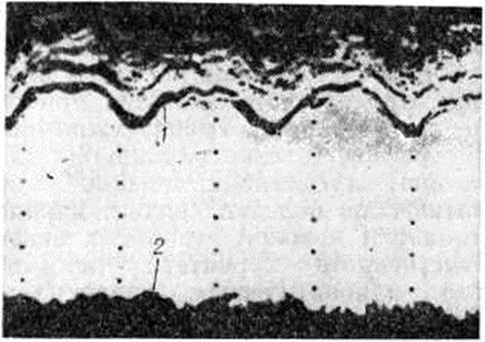

систолический шум (смотри полный свод знаний Сердечные шумы) прослушивается на аорте и может иметь различный тембр, вплоть до очень грубого при склерозе аортального клапана. Систолический шум на верхушке сердца вследствие относительной недостаточности митрального клапана прослушивается довольно часто. При развитии аневризмы в области сердца выявляется парадоксальная пульсация и выслушивается резкий систолический шум. артериальное давление может быть повышено. На рентгенограмме в переднезаднем положении ясно выступает увеличение левого желудочка, верхушка которого закруглена. При рентгенокимографии могут выявляться участки со сниженной амплитудой зубцов — постинфарктные рубцы или аневризма желудочков. Эхокардиография выявляет парадоксальное движение межжелудочковой перегородки в систолу при локализации аневризмы в перегородке в направлении от задней стенки, а не к ней, как в норме. Во время диастолы перегородка остаётся неподвижной. В случаях аневризмы или рубцовых изменений задней стенки левого желудочка иногда удаётся записать парадоксальное движение в систолу или асистолические сегменты, а также гиперкинез перегородки (рисунок 4). Для выявления локализации и объёма поражённых участков миокарда применяют ультразвуковое сканирование. Объем информации значительно возрастает при применении секторального сканирования. Регистрация в режиме реального масштаба времени, двухмерное изображение структур сердца облегчают выявление рубцовых изменений в области верхушки (рисунок 5) и передней стенки, обычно распознаваемых с трудом.